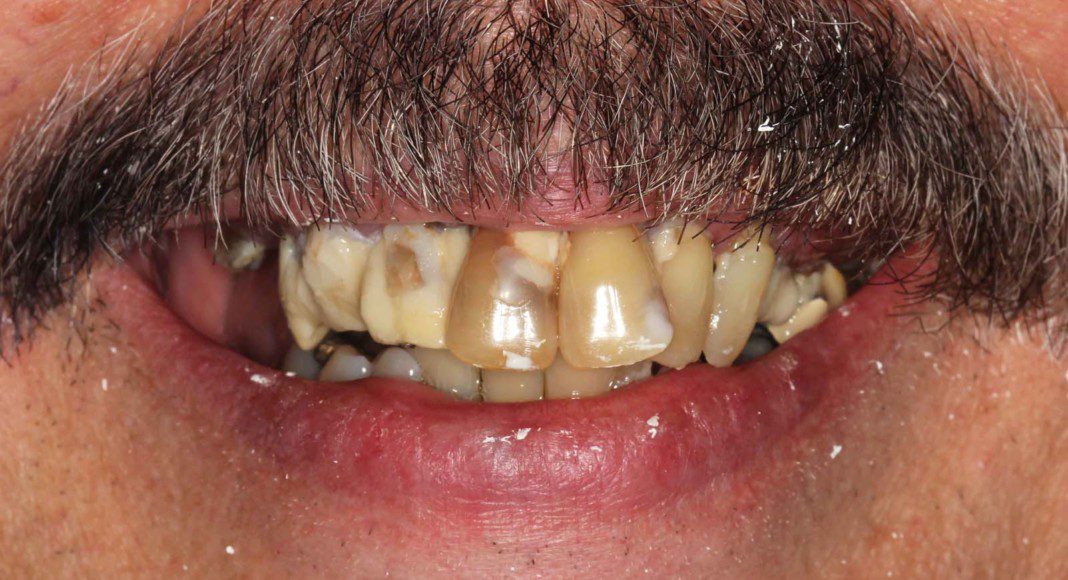

Day of surgery panoramic x-ray. Test implants were placed and adequate insertion torque was obtained (bone density and implant stability measured ≥ 25 Newton-centimeters) which qualifies multiple implants for immediate temporaries. All other teeth were extracted and a total of eight implants placed in the upper jaw (maxilla).